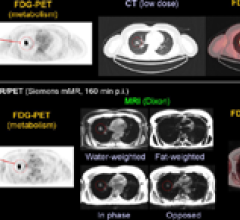

June 10, 2011 – The U.S. Food and Drug Administration (FDA) granted Siemens Healthcare 510(k) clearance for the Biograph mMR, the first system worldwide to enable simultaneous whole-body acquisition of data from magnetic resonance (MR) and positron emission tomography (PET).

June 7, 2011 — Research presented at SNM’s 58th annual meeting is taking targeted molecular imaging to a new level by combining two commonly used imaging agents into one molecular imaging procedure. The combination of these agents creates a comprehensive examination of the extent of cancer spread within a variety of organ systems in the body.